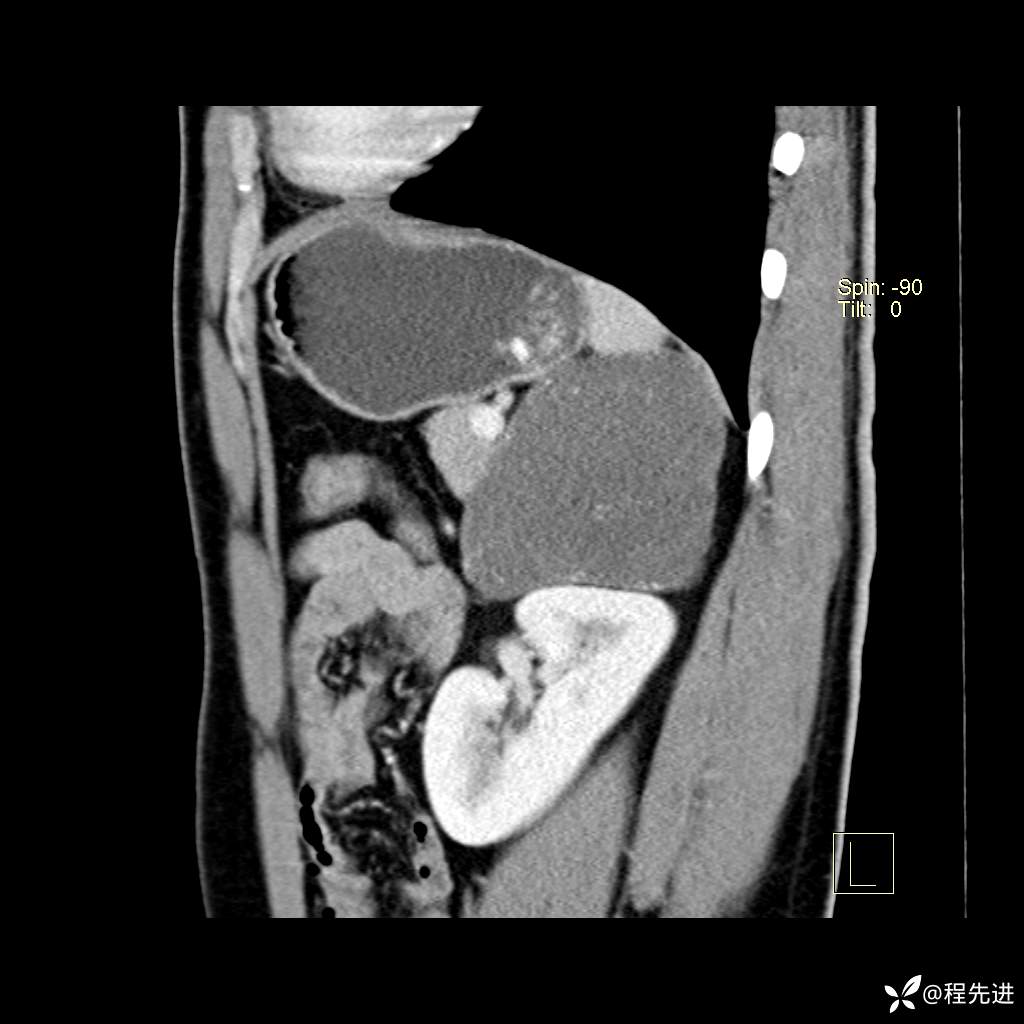

矢状位重建: